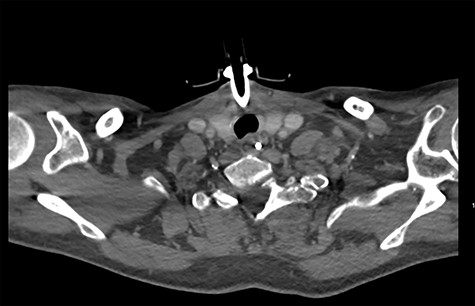

On diagnosing the right VCP, the original trauma series was reviewed by a consultant radiologist who identified a haematoma of the right carotid sheath in the neck (Fig. 1). A second CT scan of the neck and thorax was performed to determine the cause of the VCP 20 days after admission. This did not show a cause for the VCP but did demonstrate resolution of the haematoma (Fig. 2). A second FNE demonstrated resolution of the VCP 29 days following admission.

Fishman suggested that the cause of the VCP can be indicated by: the timing of events, whether it is unilateral and ipsilateral to site of line insertion, and whether the voice fails to improve within the time expected for an intubation-related injury [7]. Taking into account these factors, the clinical history, haematoma seen on the original CT, and lack of any other likely cause, the reason for the VCP was determined as neuropraxia secondary to haematoma from insertion of the central line. This reasoning was further supported by the fact that the onset and recovery of the VCP, mirrored the development and resolution of the haematoma. As, at the time of referral, the central line had been removed, this could easily have been missed as a potential cause of VCP and highlights the importance of a good history.